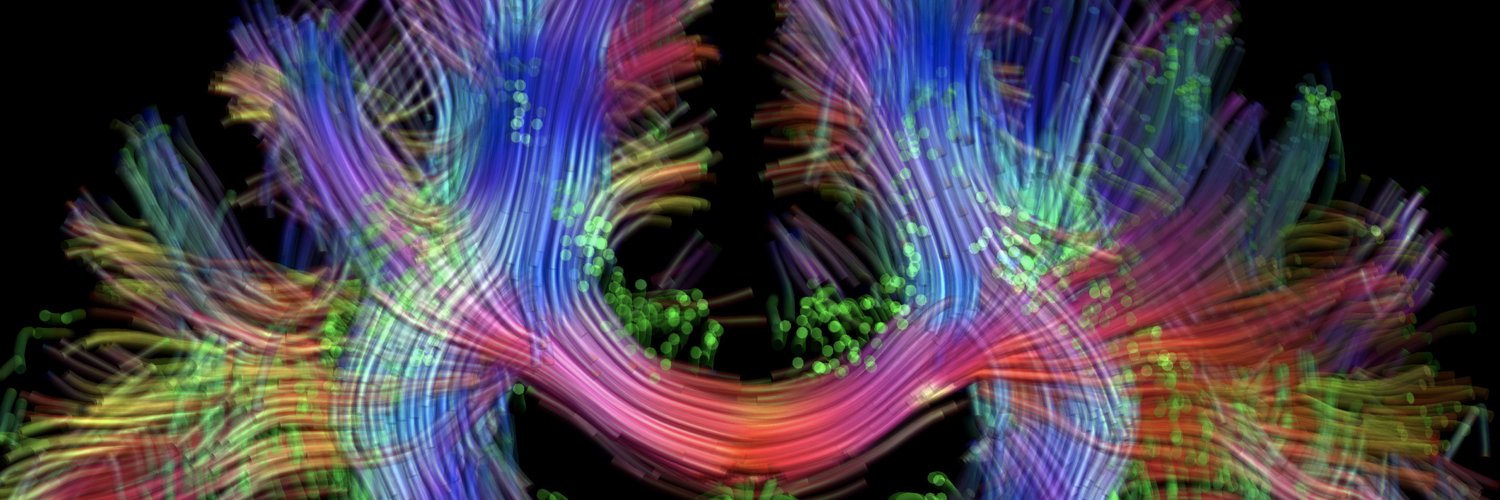

We are proud to release a 100 micron MRI scan of the human brain. Preprint on biorxiv.org/cgi/content/sh…. Videos on youtube.com/playlist?list=…. Dataset will be available in native space and MNI space at datadryad.org and integrated into lead-dbs.org. [1/2]